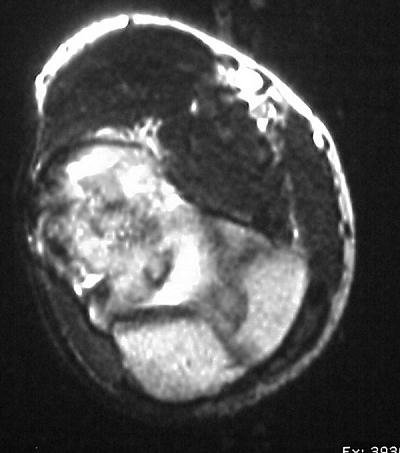

MRI shows an osteochondral sequestrum of the anterior capitellum: